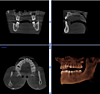

Le cabinet est équipé d’une radiologie 3D cone beam qui facilite l’étude pré-implantaire.